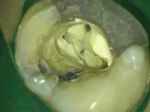

The Dental Microscope provides the dentist with unprecedented vision.

If more complicated care is required such as crowns or root canal treatment, we can provide this with improved accuracy and optimise the treatment.

The microscope has an integrated medical grade video camera so we can demonstrate live images to explain treatment decisions.